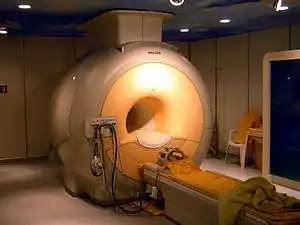

Liquid helium is used in cryogenics (its largest single use, consuming about a quarter of production), and in the cooling of superconducting magnets, with its main commercial application in MRI scanners. Helium's other industrial uses—as a pressurizing and purge gas, as a protective atmosphere for arc welding, and in processes such as growing crystal to make silicon wafers—account for half of the gas produced. A small but well-known use is as a lifting gas in balloons and airships.[20] As with any gas whose density differs from that of air, inhaling a small volume of helium temporarily changes the timbre and quality of the human voice. In scientific research, the behavior of the two fluid phases of helium-4 (helium I and helium II) is important to researchers studying quantum mechanics (in particular the property of superfluidity) and to those looking at the phenomena, such as superconductivity, produced in matter near absolute zero.

While balloons are perhaps the best known use of helium, they are a minor part of all helium use.[74] Helium is used for many purposes that require some of its unique properties, such as its low boiling point, low density, low solubility, high thermal conductivity, or inertness. Of the 2014 world helium total production of about 32 million kg (180 million standard cubic meters) helium per year, the largest use (about 32% of the total in 2014) is in cryogenic applications, most of which involves cooling the superconducting magnets in medical MRI scanners and NMR spectrometers.[158] Other major uses were pressurizing and purging systems, welding, maintenance of controlled atmospheres, and leak detection. Other uses by category were relatively minor fractions.[157]

Helium at low temperatures is used in cryogenics, and in certain cryogenics applications. As examples of applications, liquid helium is used to cool certain metals to the extremely low temperatures required for superconductivity, such as in superconducting magnets for magnetic resonance imaging. The Large Hadron Collider at CERN uses 96 metric tons of liquid helium to maintain the temperature at 1.9 K (−271.25 °C; −456.25 °F).[175]